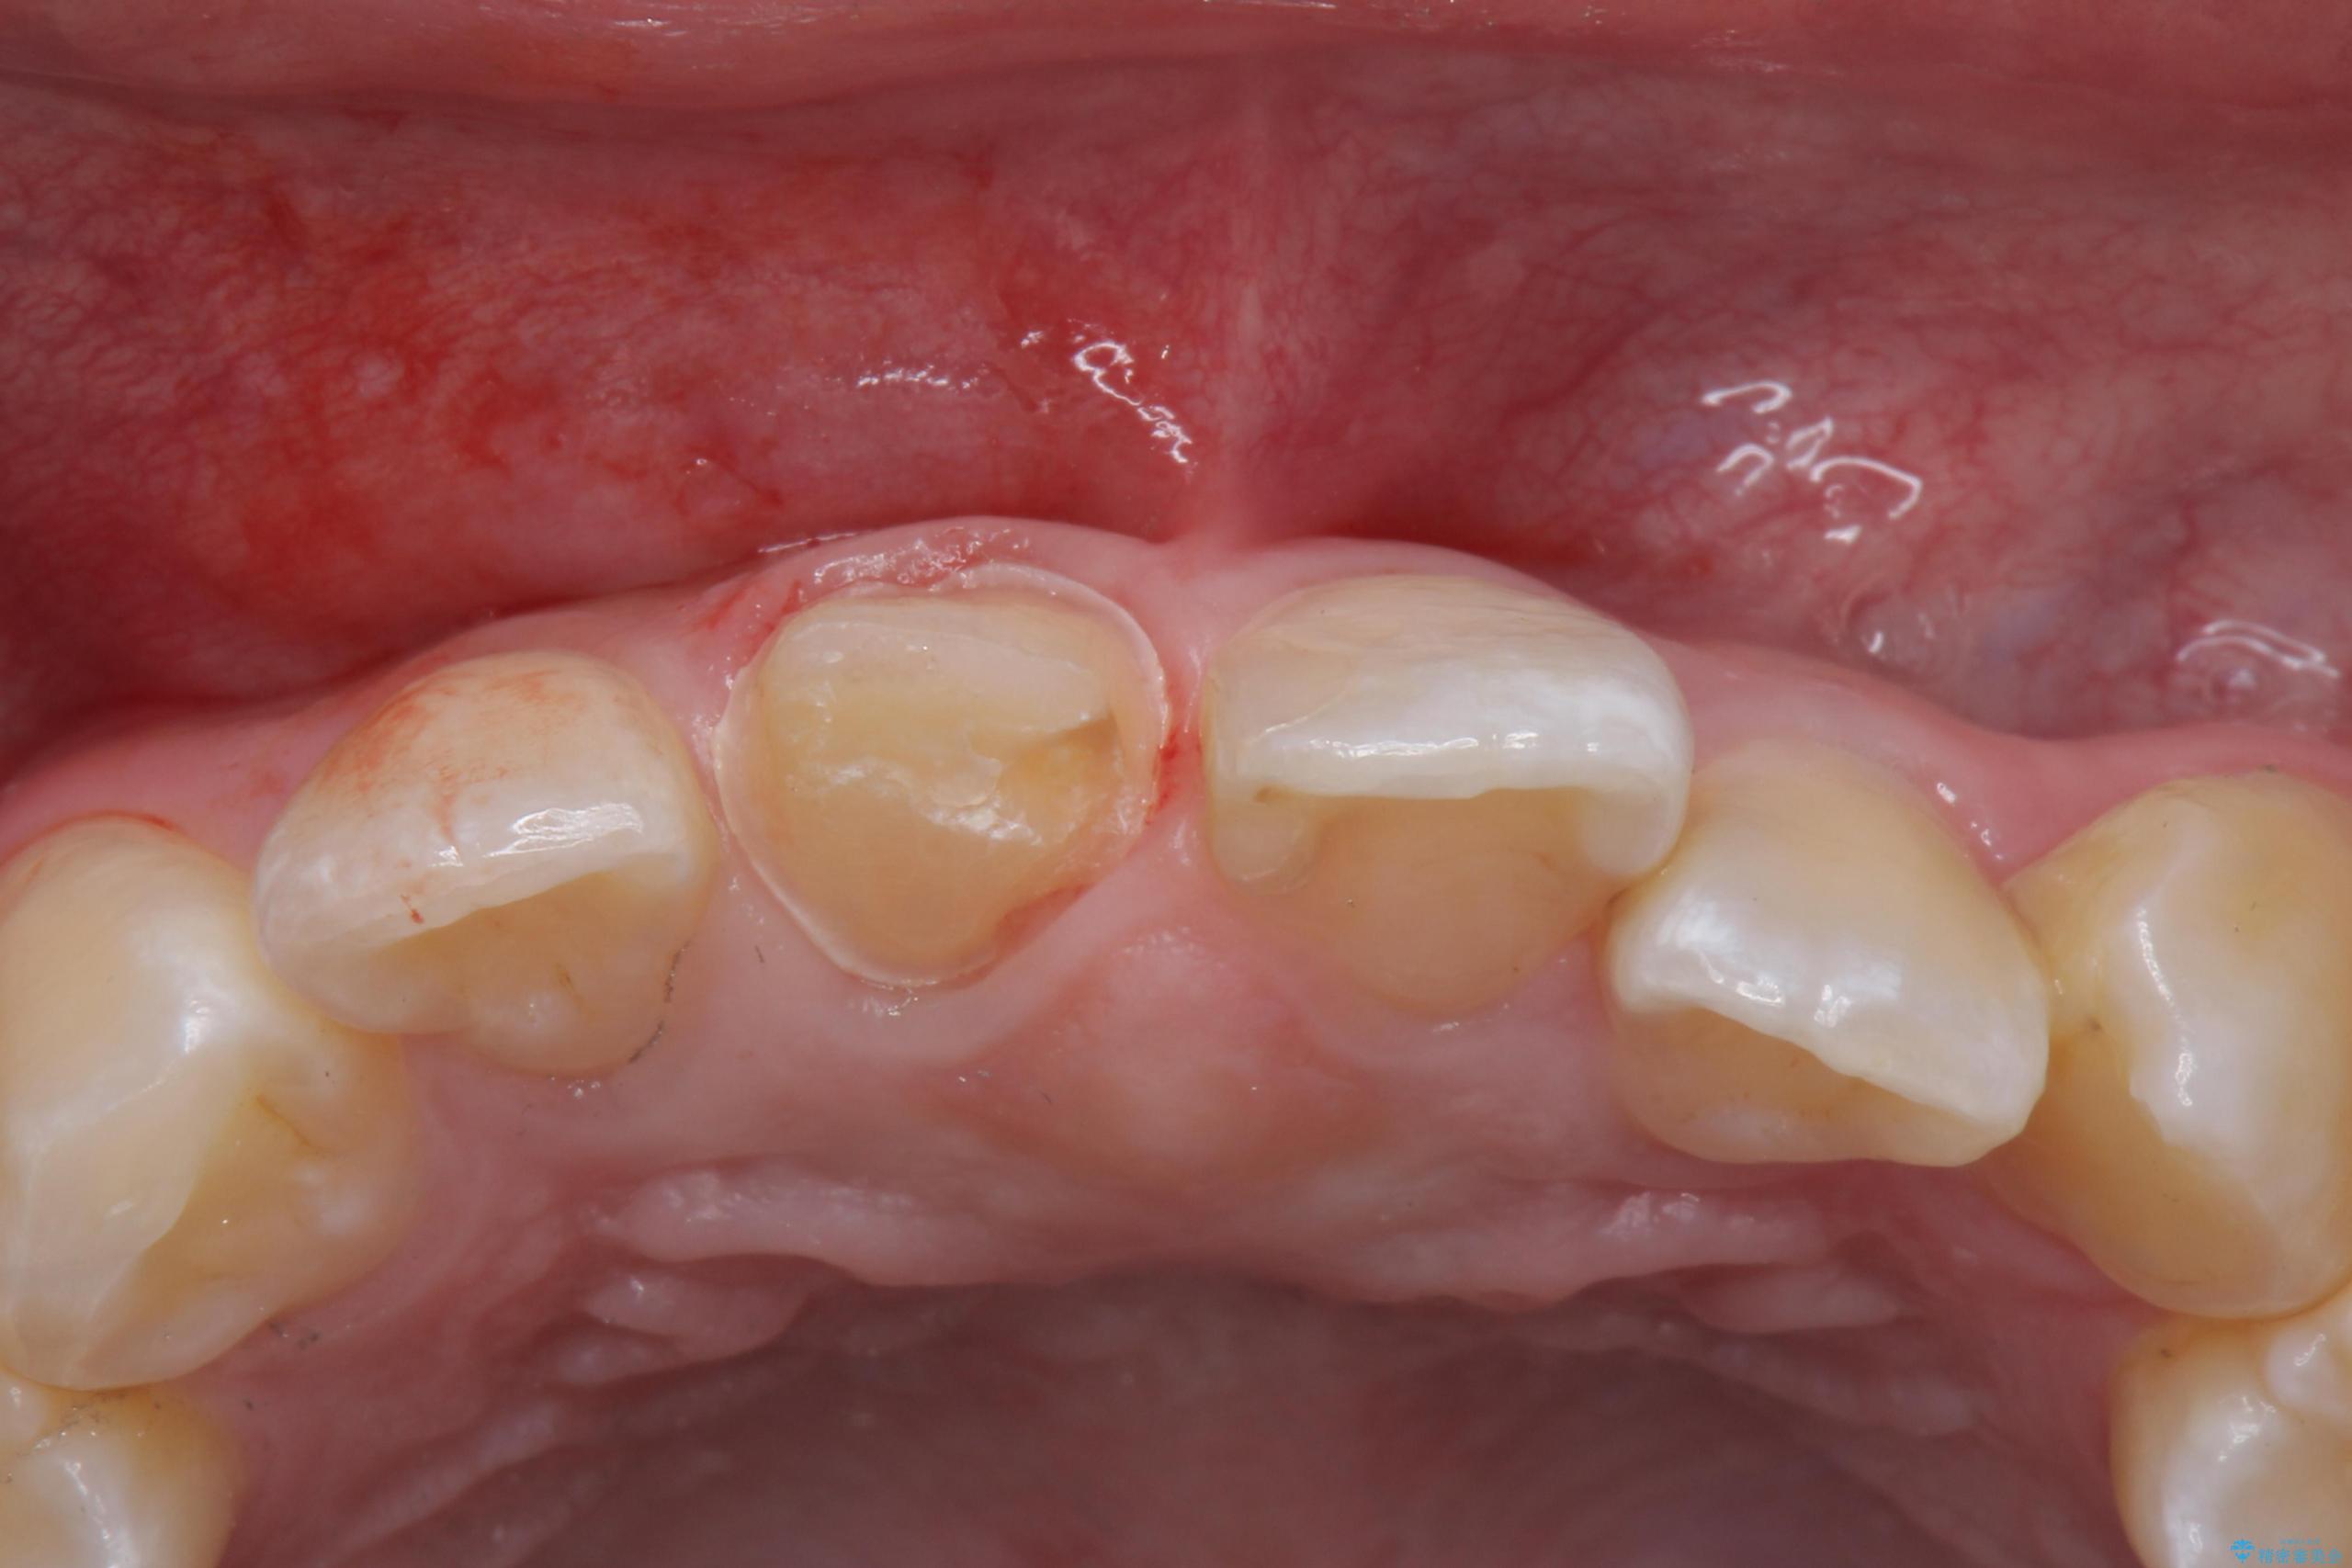

- 前歯のかぶせ物の色が気になるとのことで来院された患者様です。

セラミッククラウンで作り変えていきます。

- 右上1: 仮歯/11,000円、ジルコニアクラウン(スタンダード)/121,000円 合計132,000円(税込)費用は治療当時の料金となります